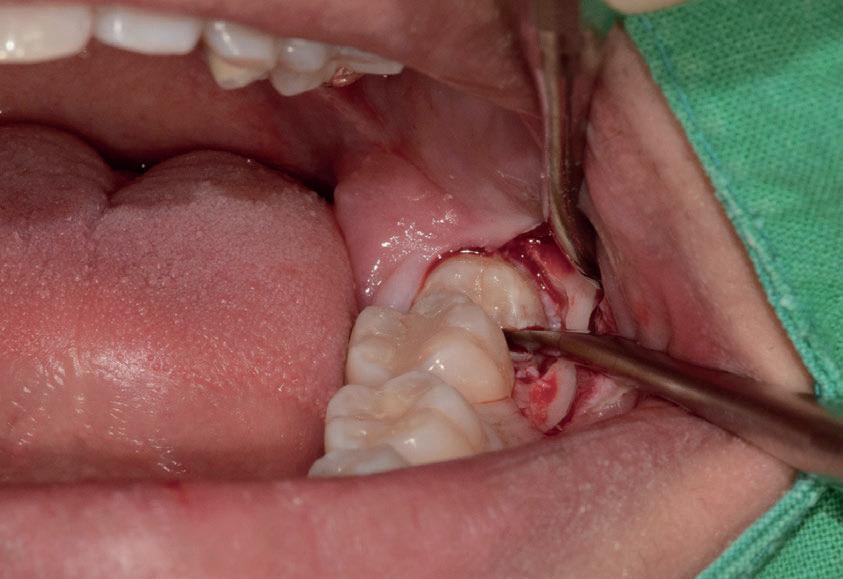

L’estrazione di un dente del giudizio incluso orizzontalmente, sfruttando questa tecnica con il manipolo dritto, richiede un’ulteriore rimozione di struttura dentale e di osso. Figg. 180-183

Per questo motivo, il lembo deve essere esteso fino al primo molare e bisogna avere una visione del sito chirurgico adeguata. Più il dente è inclinato orizzontalmente più la rimozione di osso vestibolare è necessaria.

Solitamente viene utilizzata una fresa a fessura dritta da manipolo per sezionare le radici, ma è preferibile usare una fresa rotonda laddove c’è la necessità di rimuovere l’osso alveolare attorno alla corona, come mostrato in fotografia. Figg. 184-187

In questo caso la separazione del periostio e la rimozione di osso vestibolare è quasi inevitabile per estrarre il #38.

Figg. 180-187 - Un caso di un’estrazione di un dente del giudizio, utilizzando il manipolo dritto. Fig. 180 Fig. 181 Fig. 182 Fig. 183 Fig. 184 Fig. 185 Fig. 186 Fig. 187